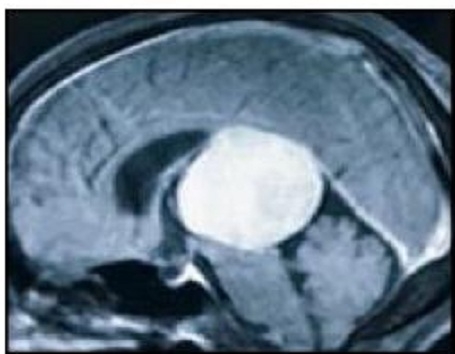

MRI Brainscans showed a gianttumour (6.7 x 5.6 x 5.5 cm ) in the centre of the brainwithinthe third ventricle. She underwent a surgical excision for the same. Post-operation, the patienthadcompleteimprovement in headache andatpresent shehas mildimprovingweaknessintheleft upper and lower limbs. Velum Interpositum Meningiomas (VIM) are very rare group of tumours. To our knowledge, this is the largest VIM in neurosurgical literature to be operated in the geriatric age group. In common man terms, the tumour was nearly about the size of a standard tennis ball.The proximity to the critical neurovascular structures makes this tumour one of the most challenging cases for theneurosurgeon.Literatureanalysis shows that a total of less than 10 cases have been reported in the geriatric age group.